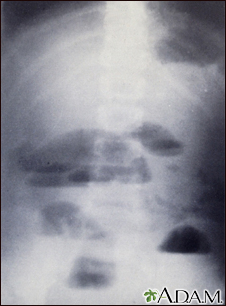

Small bowel obstruction - x-ray

X-rays of the abdomen are important in diagnosing the presence of small bowel obstruction. When obstruction occurs, both fluid and gas collect in the intestine. They produce a characteristic pattern called "air-fluid levels". The air rises above the fluid and there is a flat surface at the "air-fluid" interface.